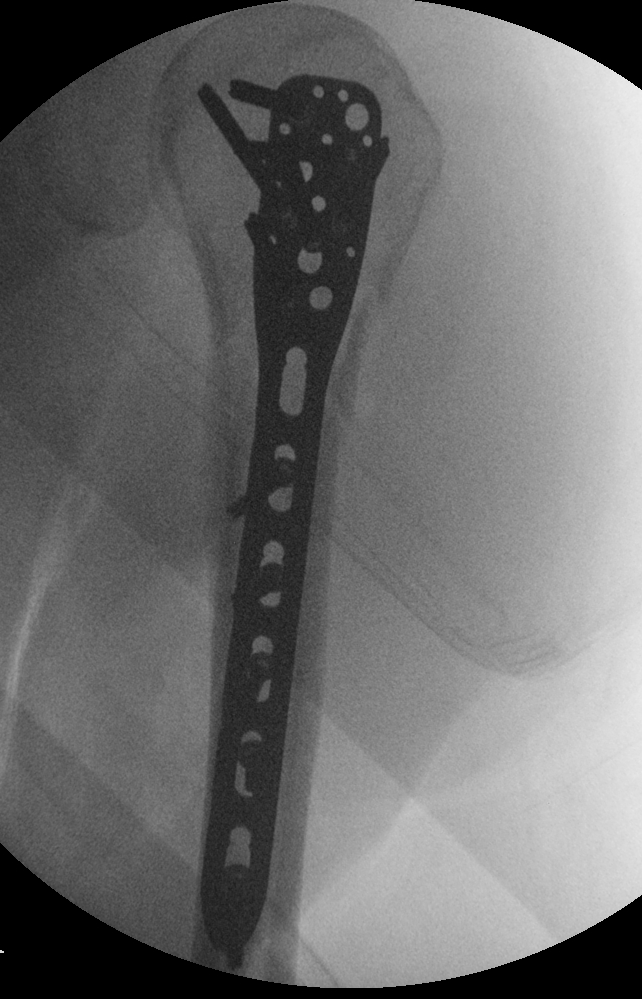

Have spent the last week as a "Boneless Chicken". What little unstrapped moments I had - the half after the fall, change of shirt once - my arm felt like it just dangled there. I t had no feeling but pain; no substance. The Xray from a week ago gave only an angle that shows the bone as a split, perhaps a huge split, but still some connection. Today's new pic show a 3/8" gap completely through and an alignment that isn't "true". That made the risk of surgery much easier to opt for.

Nearly 2in screws into a stainless steel cover plates now joins my upper left humerus. MUCH better than being relegated to the Ranch.

Oh, I've been asked when the screws come out. Let's hope they never do . . . .